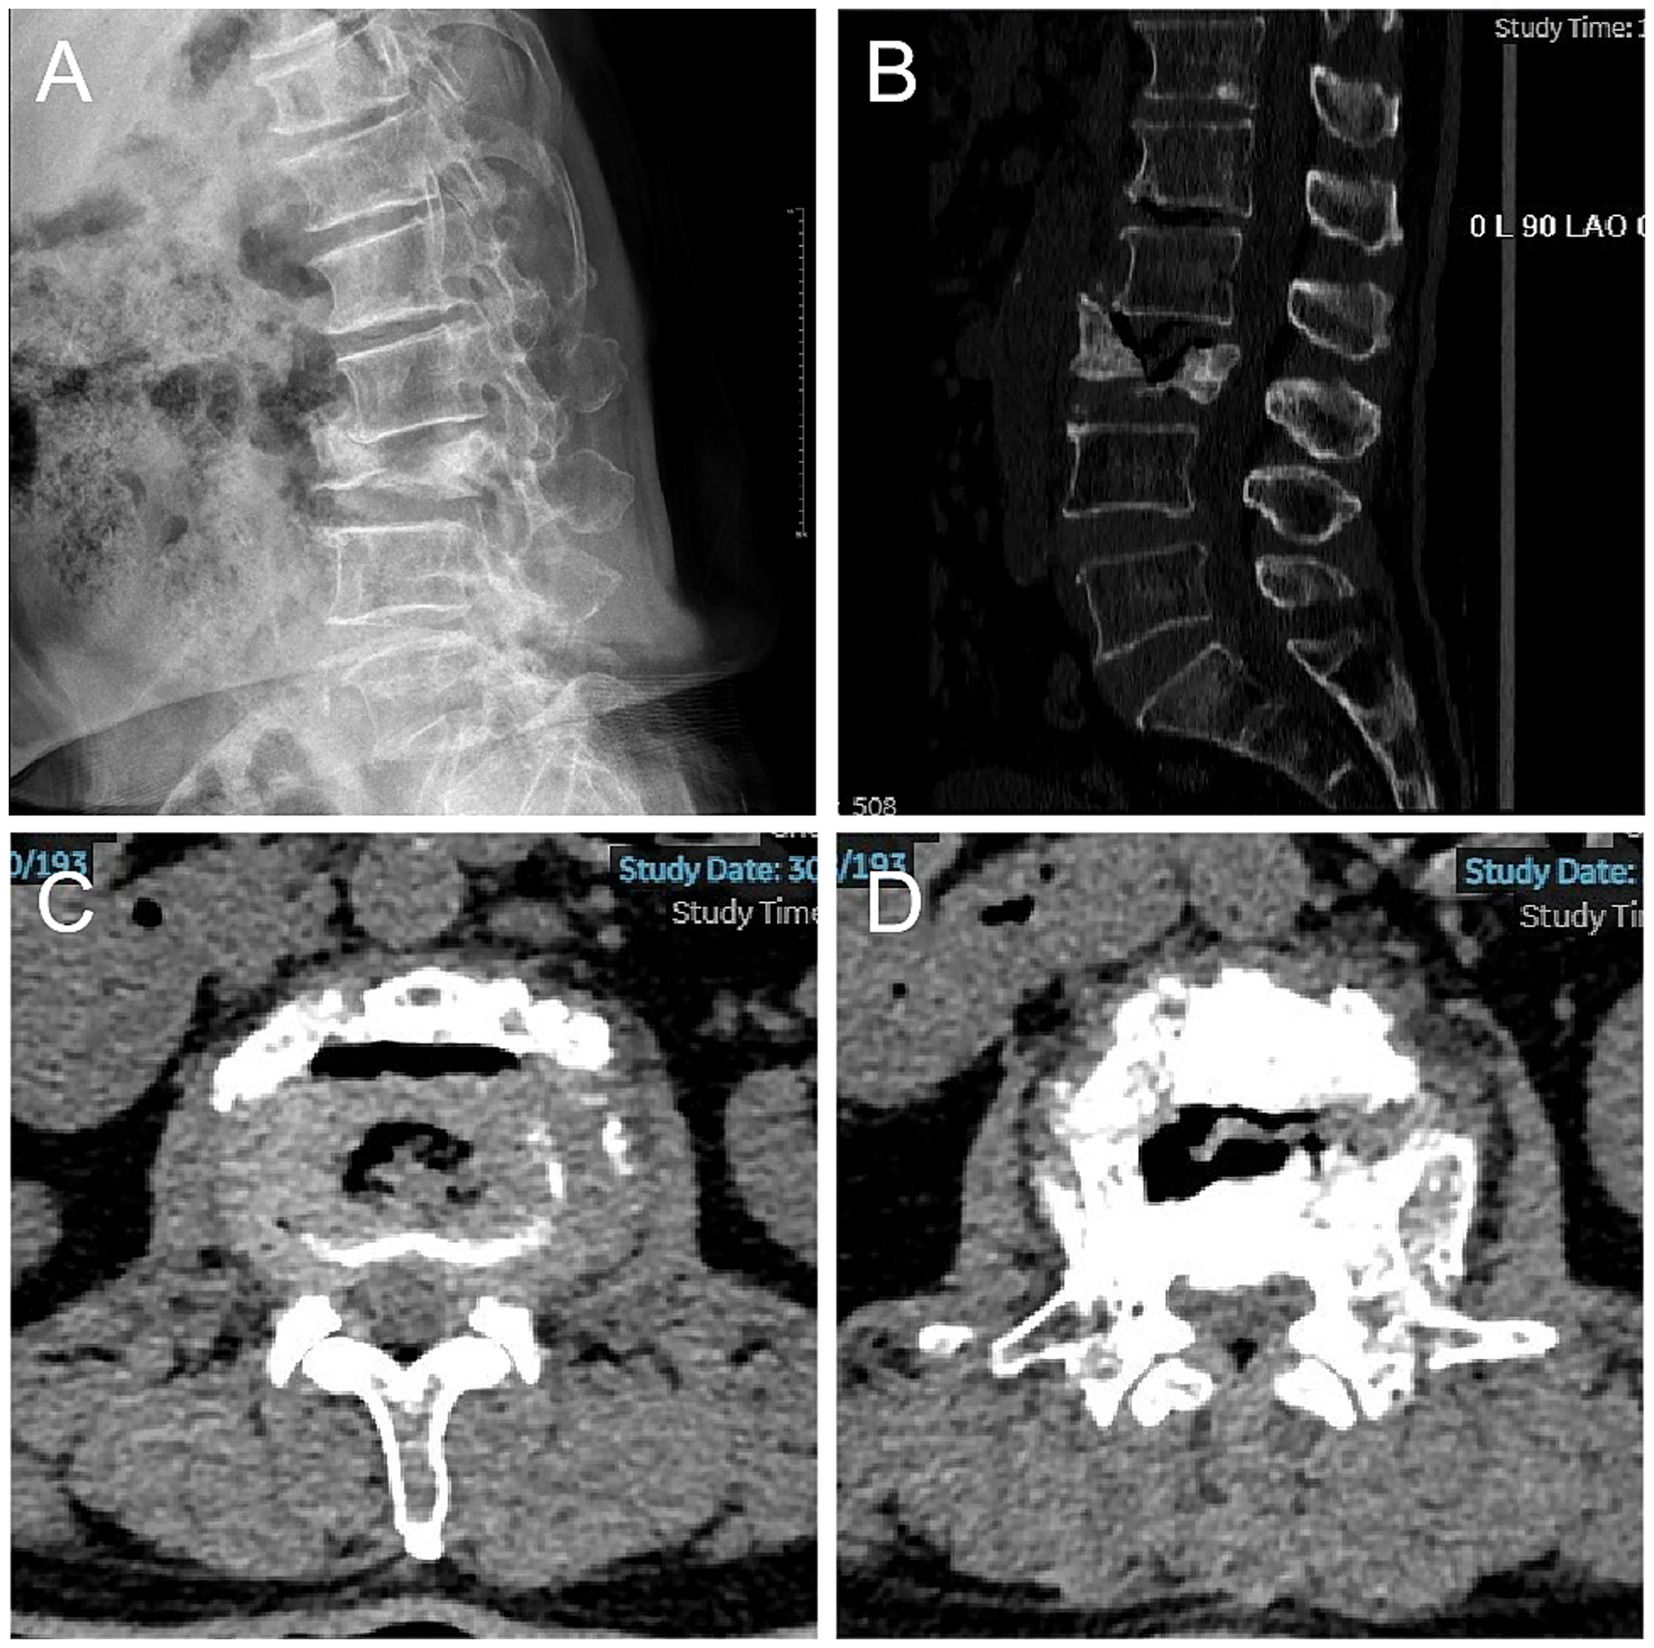

Figure 2

Surgical procedure. (A) Exposure of the attachment of the ligamentum flavum. (B) Bony decompression of the medial superior articular process with a Kerrison rongeur to decompress the traversing nerve root. (C) Probing of the lateral aspect of the nerve with a dissector to confirm adequate decompression. (D) Ipsilateral discectomy for decompression. (E) The nerve root is freely mobile and the dural sac is well expanded. (F-J) Through the working cannula, via the channel used for decompression, the bone cement injector is guided into the vertebral body, and the bone cement is continuously injected, accompanied by biplanar fluoroscopy to avoid leakage of the bone cement, until the bone cement fills the vertebral body and the intervertebral disk. (K) Solidified cement under endoscopic visualization. (L) Surgical specimen.

Then, the endoscope was withdrawn while the working cannula was maintained in position. A balloon catheter was introduced through the working cannula and advanced along the percutaneous endoscopic decompression corridor to the L2/3 intervertebral disk, then directed across the disk space (disk–vertebra route) into the L3 vertebral body. The balloon dilatation compacts the cancellous mass within the vertebral body to form a cavity. Bone cement (polymethylmethacrylate, PMMA) was then prepared and injected into the L3 vertebral body through the same channel under biplanar fluoro, completing PKP. To correct the focal kyphotic deformity in order to relieve foraminal compression, additional bone cement was injected into the L2/3 disk using the same channel, completing PCD (Figure 2). During both kyphoplasty and discoplasty, cement was delivered in small incremental aliquots of approximately 0.2–0.3 mL under continuous biplanar fluoroscopic monitoring, and injection was stopped once the planned filling pattern was achieved.

The position and distribution of the cement were meticulously monitored with biplanar fluoroscopy to prevent leakage. The incision was closed with a single stitch, and no drainage was required. The total operative time was 105 min, and the estimated blood loss was less than 10 mL. After recovering from anesthesia, the patient experienced significant relief from lumbar and bilateral lower limb pain, with muscle strength returning to normal levels. On the second day postsurgery, the patient was able to ambulate independently with lumbar support. On postoperative day 4, imaging confirmed resolution of the focal kyphotic deformity. The patient was subsequently discharged with stable blood glucose and blood pressure (Figure 3). A one-month follow-up revealed that the patient had made a full recovery, as indicated by the absence of any abnormal symptoms or signs. The VAS score was 1, and the JOA score was 23. Fourteen months following the surgical intervention, the subsequent evaluations revealed no significant variations from the preceding assessments, with no complications observed.